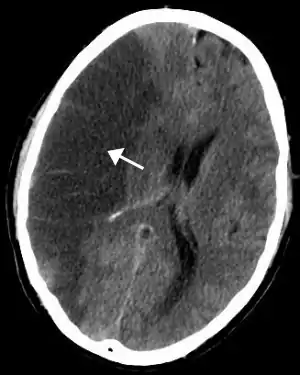

![]() Scanare tomografică a creierului, putându-se observa ischemia cerebrală în emisfera dreaptă | |